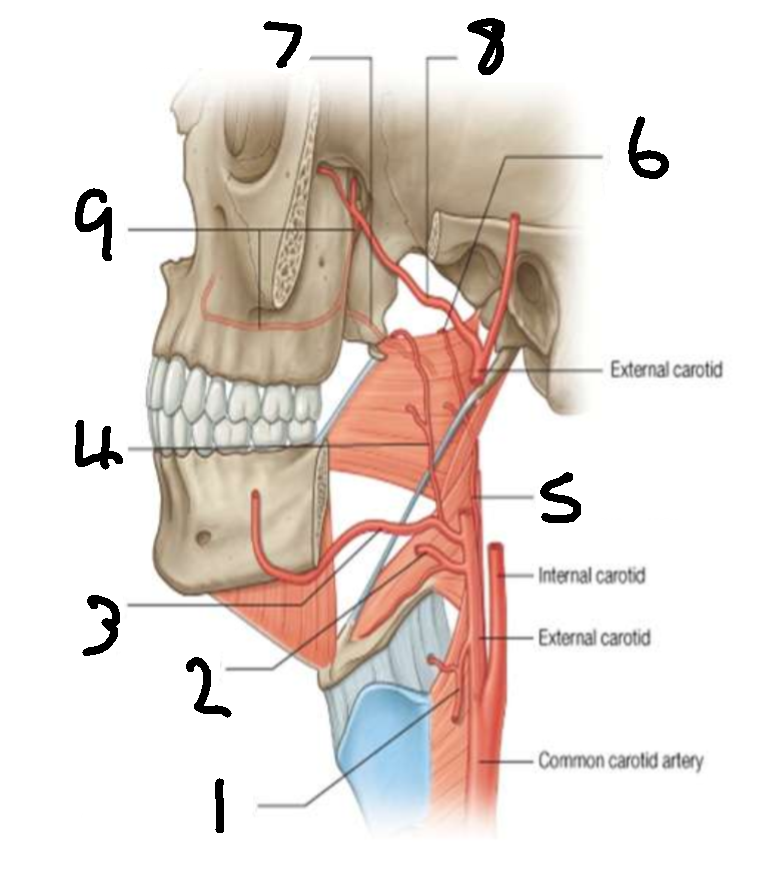

What is 1?

superior thyroid artery

What is 2?

lingual artery

What is 3?

facial artery

What is 4?

ascending palatine artery

What is 5?

ascending pharyngeal artery

What is 6?

palatine branch of pharyngeal artery

What is 7?

lesser palatine artery

What is 8?

maxillary artery

What is 9?

greater palatine artery